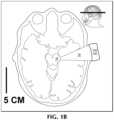

FIG.1B shows the transducer system targeted at the hippocampal formation and entorhinal cortex.

FIG.1B shows an axial section through the mesial temporal lobe andTNS100 targeted at the hippocampal formation andentorhinal cortex34.Targets34 are deep below the temporal ultrasound window in the 3.5 to 5 cm range from the surface.TNS100 may focusultrasonic waves30 ontarget34 for patients with Alzheimer's disease or other degenerative conditions with predominant memory loss symptoms (amnestic syndrome). These cases are characterized by amyloid deposits that disrupt the mesial temporal structures.